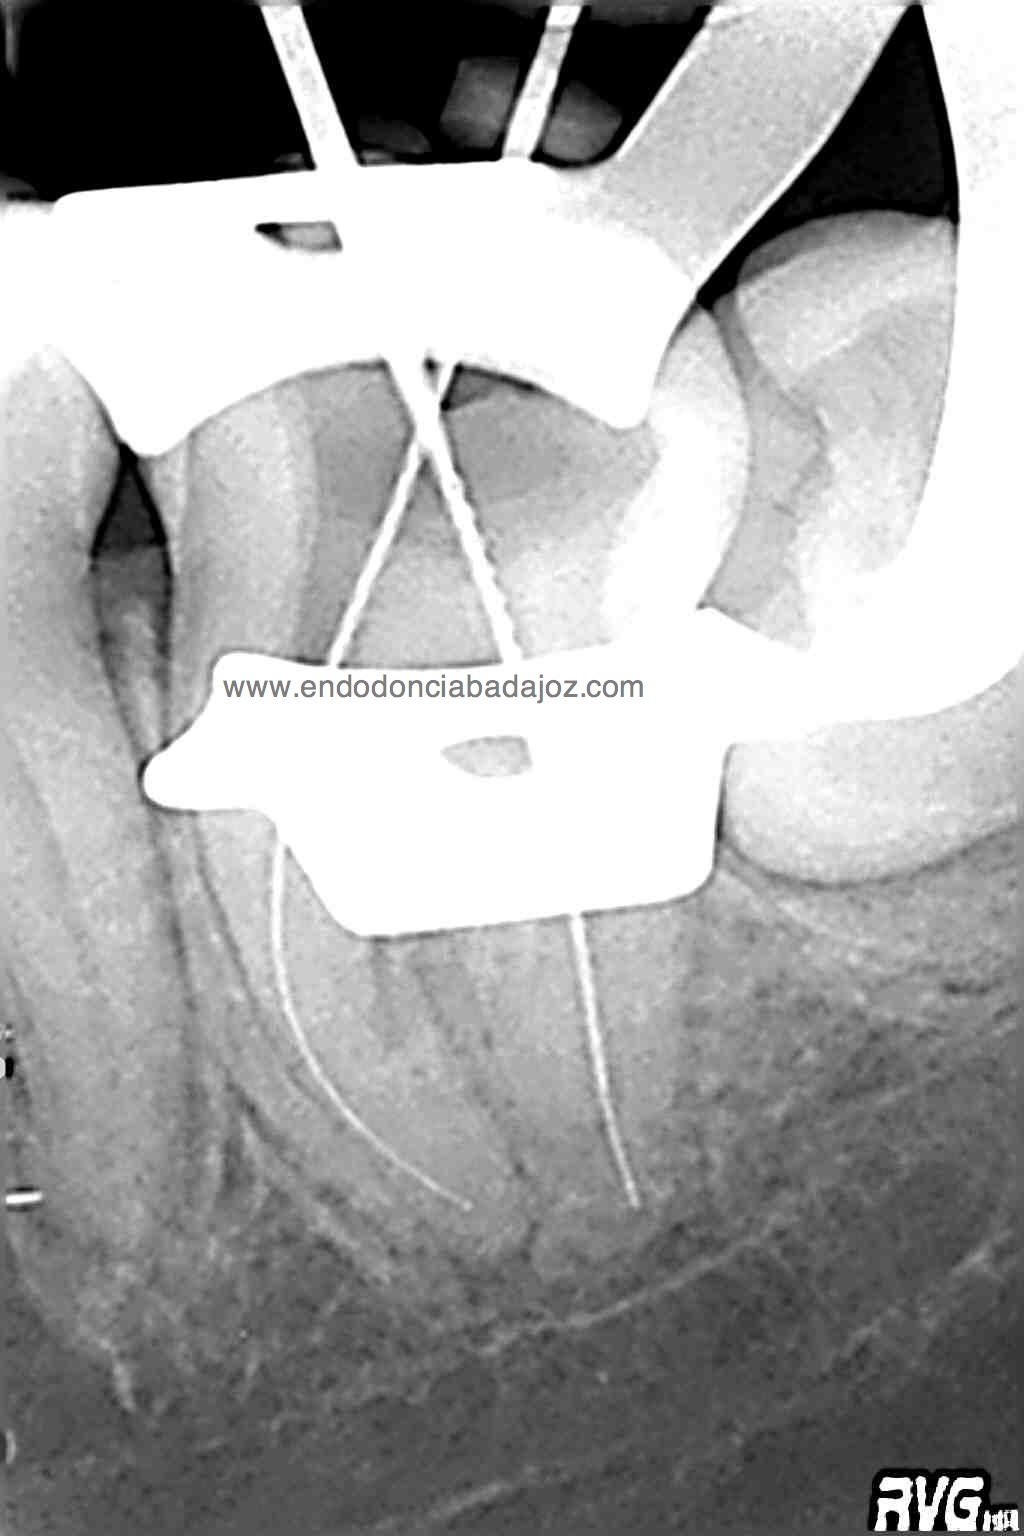

Después de haber instrumentado con un sistema Protaper, y habiendo estandarizado el conducto en un 25mm en apical y una conicidad del 6% con limas K3. observé que el conducto Distal presentaba otro conducto Disto-Vestibular cuya entrada estaba en la pared del conducto Disto-Lingual tratado, bastante complicado de trabajar.

Observando la Rx pude verificar y diferenciar las raices:

Abrimos el conducto distal con ultrasonidos haciendo la entrada al conducto Disto-Vestivular más recta.